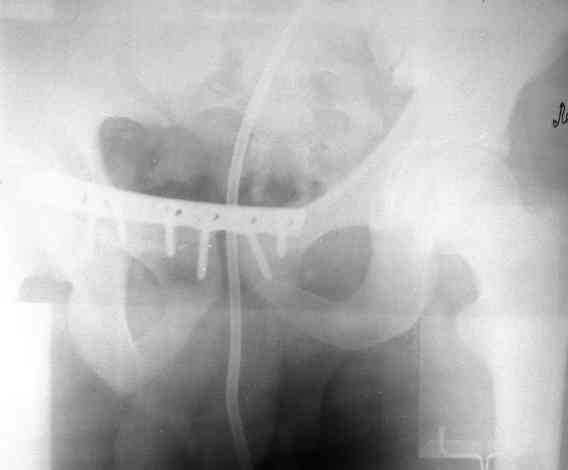

Уважаемые коллеги! На днях оперировал перелом таза месячной давности - разрыв симфиза, перелом обеих ветвей правой лонной кости, трансфораминальный перелом крестца слева. Представляю рентгенограммы с задержкой - технические причины.

Предоперационные рентген и КТ, в операционной - снимки после каждого фиксатора. Вертикальное смещение полностью устранить не удалось. В первую очередь за счет заднего полукольца. Хотя при компрессии на стержнях горизонтальное смещение было сантиметра 1,5. Т.е. крестец, на мой взгляд еще не сросся. От коллег хотел-бы услышать допустима-ли такая остаточная деформация?

Спасибо за обсуждение и ссылку. Во время операции, как я уже говорил, удалось дать приличную встречно-боковую компрессию. Неврологии у пациента не было и нет. Это и побудило сильно не усердствовать с репозицией трансфораминального перелома. На фоне фиксации спереди двумя пластинами, надеюсь, крестец срастется. Как будет возможность представлю контрольные КТ.